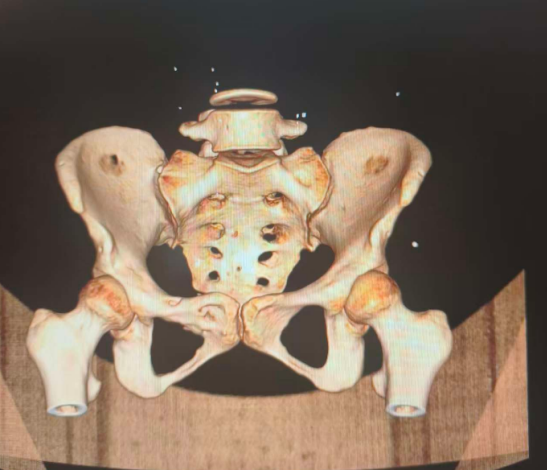

为了获得直观印象,先上一张图:这是骶髂关节,它的主要作用是稳定骨盆并缓冲上半身重量传递至下肢时的冲击力。

图片